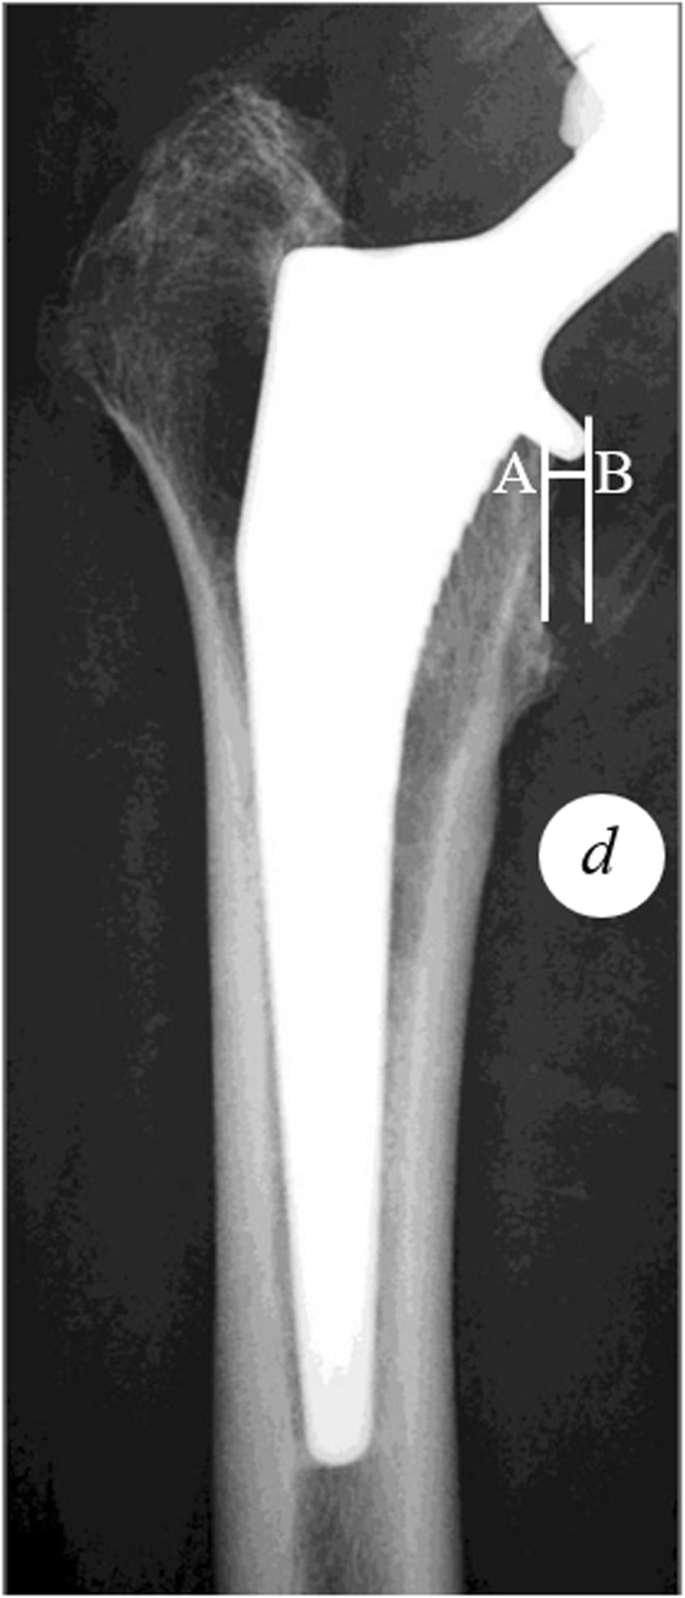

Stem alignment was evaluated on postoperative AP radiograph of the femur, according to the intersection angle between vertical axis of the stem and diaphyseal femoral axis. A positive value represents valgus alignment of the femoral stem, and vice versa. Furthermore, we introduced a variable termed collar protrusion length (CPL) to evaluate the severity of collar protrusion. On the postoperative AP radiograph, CPL was measured as the distance between the medial aspect of the metal collar and the medial aspect of the calcar (Fig. 2). A true CPL can be obtained after correcting the magnification error. In terms of CPL, a positive value represents an overhang of the collar, and a negative value represents that the collar stays within the calcar region.

Measurement of collar protrusion length (CPL). Point A represents the medial aspect of the calcar and point B represents the medial aspect of the metal collar. d represents the diameter of coin measured on the X-ray. CPL was measured as the distance between the vertical line across points A and B, after correction for magnification. A positive CPL represents overhang of the collar over the calcar